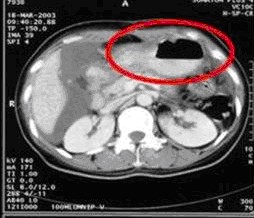

病例1 女,49歲。胃體癌晚期,胃竇增厚強(qiáng)化,與周圍粘連,腹膜增厚,腹腔廣泛轉(zhuǎn)移,伴大量腹水。放/化療失敗,無法手術(shù)。治療方案:腹腔灌注今又生2×1012VP/2次/周,共12周,同時灌注順鉑和5-氟尿嘧啶腹腔,后4…今又生治療病例---頭頸部腫瘤